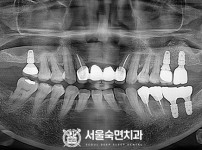

임플란트-전후사진3

치과를-선택할-때-꼭-확인하세요-서울숙면치과-임플란트-전후사진